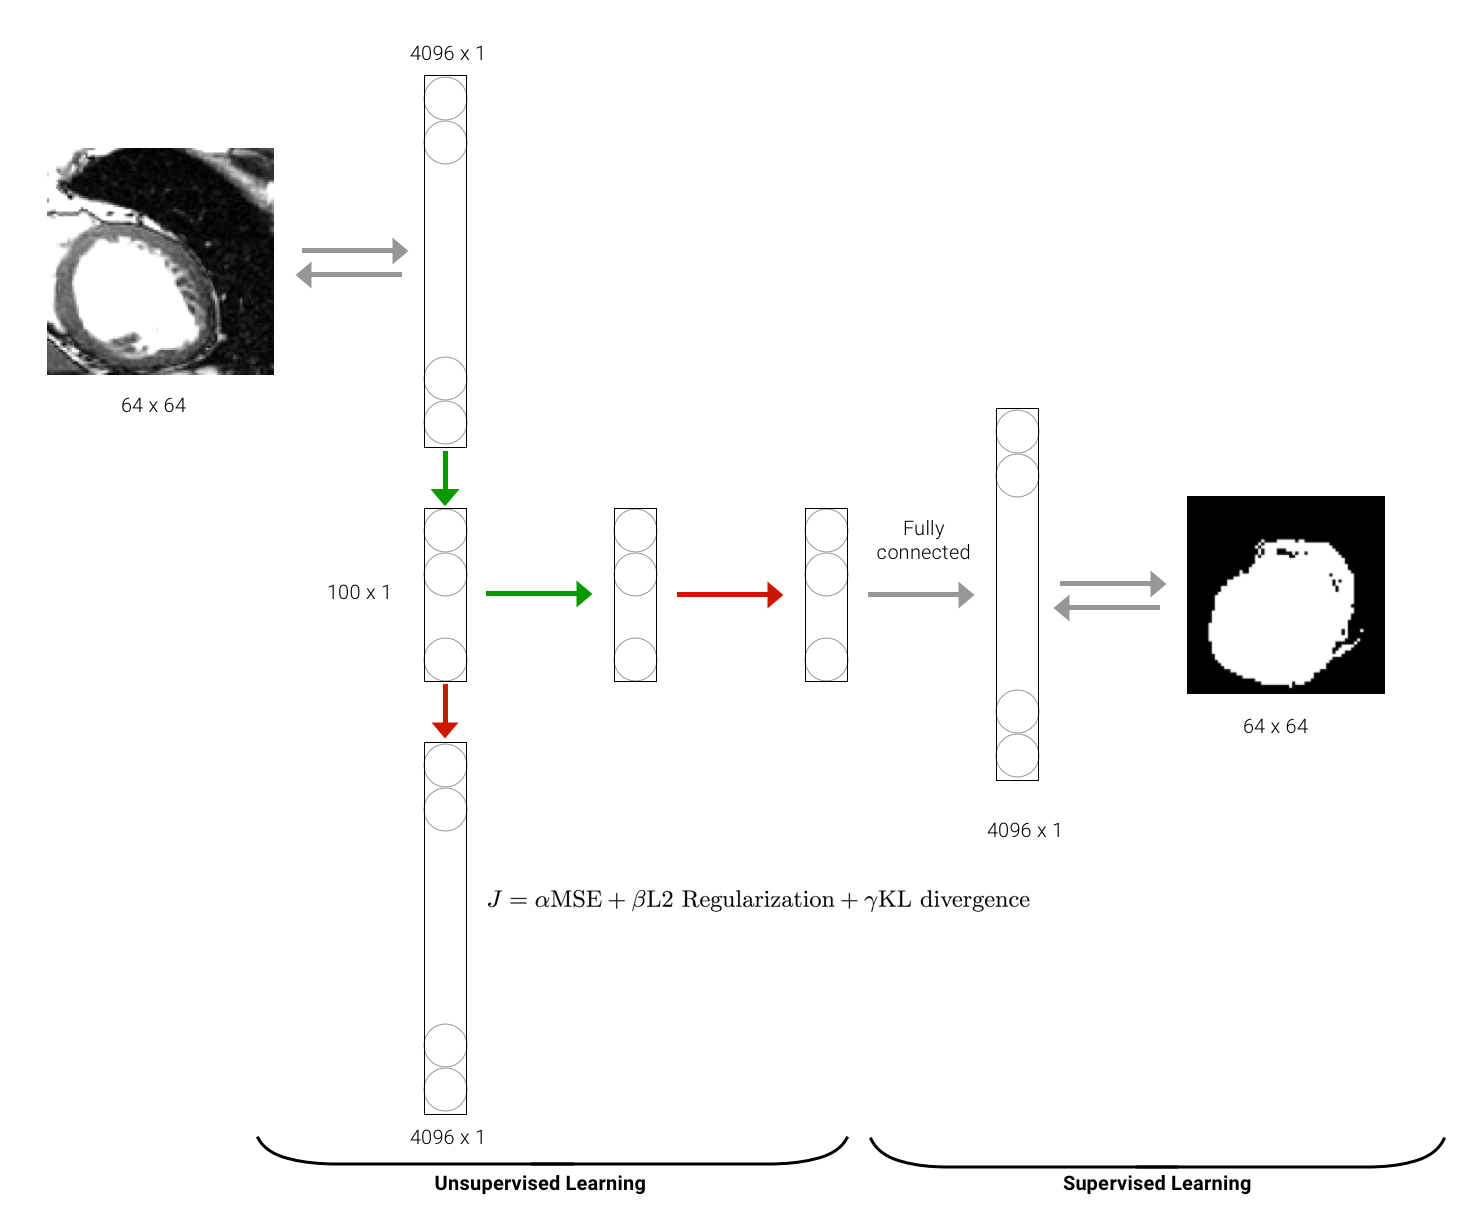

Concretely, we want to locate the exact contour of the LV in the bounding box obtained using CNN. In order to do so, we train a stacked AutoEncoder following two steps : an unsupervised learning step for the training of two sparse auto-encoders that are stacked (the second AutoEncoder uses the output of the first AutoEncoder hidden layer); and a supervised learning step for the training of a fully connected layer (using the output of the second AutoEncoder hidden layer). The architecture is represented in the block diagram Figure 6.

Thus, the stacked auto-encoder we are using has one input layer (the ROI) of shape sub-sampled to and unrolled to ; two hidden layers of size each; and one output layer of shape which is re-rolled in order to obtain the binary mask of the contour of shape .

For the unsupervised learning part, the objective is to minimize the loss of the model which is, in our case, a customized loss that combines Mean Square Error (MSE), -regularization and Kullback Leibler (KL) divergence. The use of such a loss allows avoiding overfitting (-regularization in order to decrease the magnitude of the weights) as well as learning higher representations of the Region of interest (sparsity constraints using KL divergence).

Concerning the supervised learning task, we train a fully connected layer using the last representation of the Region of Interest (output of second AutoEncoder) and predict the inferred shape using manual delineation done by experts (ground truth).

Customizing the loss of our neural network can totally change the performance of our approach in both ways [9]. Let’s recall that the method uses a customized loss for the two stacked autoencoder (weighting between Mean Square Error (MSE), regularisation and Kullback-Leibler (KL) divergence) in the unsupervised learning step and a regular MSE for the last fully connected layer in the supervised learning step. We test another alternative where all the losses are MSE and plot the contours from the manually segmented LV, the prediction with and without active contour models in Figure 6. As we can see, the contour is smoother and seems to fit the ground truth while having a meaningful shape (not shrinking or leaking or irregularities).